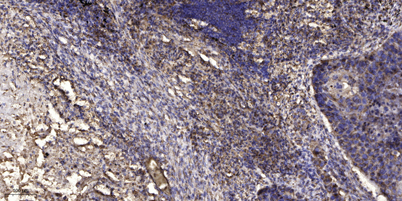

Immunohistochemical analysis of paraffin-embedded human Squamous cell carcinoma of lung. 1, Antibody was diluted at 1:200(4° overnight). 2, Tris-EDTA,pH9.0 was used for antigen retrieval. 3,Secondary antibody was diluted at 1:200(room temperature, 45min).